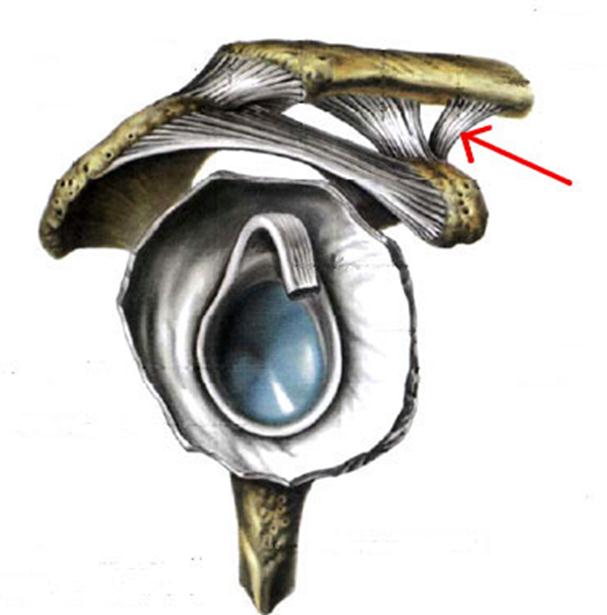

S: Стрелка указывает на... плечевой кости.

+:tuberculum majus

-:tuberculum minus

-:epicondylus medialis

-:troсhlea

-:capitulum